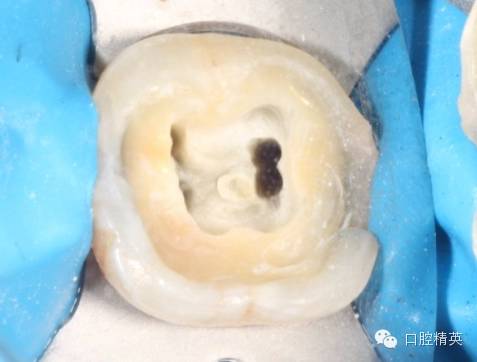

然后开始去腐,我习惯用金刚砂球钻先从边缘去腐,最后开髓,最好不要用裂钻直接开髓,第一可以避免底穿,第二避免腐质飞沫污染髓腔,给rct带来麻烦。

![36的一次性根充]()

开髓,揭净髓顶,直线通道车针逐步建立直线通路,大量次氯酸钠冲洗,探查根管长度,次氯酸钠和edta交替冲洗根管

tf镍钛锉预备至30#06锥度(虽然根尖区域的预备应该在35#~40#)但我认为这不是根尖周炎,所以仅仅预备到30#,大量次氯酸钠荡洗根管,根充还是用的iroot糊剂和热牙胶,我用的是思博安的热牙胶,很多同行和我说,相比韩国的产品思博安的成本太高了,但思博安的牙胶是 β象限的,低温时的流动性更好,更容易进入狭窄部位和侧支根管,所以我认为,相对与更好的治疗效果,成本并不重要。

近中根管的侧枝清晰可见